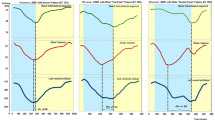

Phase analysis

Phase images were created using a first-order harmonic fit of the time–activity curve for each pixel, representing the timing of ventricular contraction relative to the R wave of the ECG.26,27 The phase angle defines the point in the time–activity curve where the Fourier function reaches its peak, representing the onset of contraction. An example of a phase and amplitude image with the associated time–activity curve and phase histogram for a patient with normal ventricular contraction is shown in Figure 1. The R–R duration is measured in seconds but can be converted to degrees, where 360° represents the length of one cardiac cycle. Any areas of dyssynchronous contraction will appear as delays in the phase images and phase histogram.

Comparison was made pre and post beta-blockade as summarized in Table 3. There was a significant improvement in all of the dyssynchrony parameters and LVEF measured post beta-blockade. The only parameter that did not significantly improve after beta-blockade was ApEn for the non-ischemic group. There was no significant difference in dyssynchrony between the ischemic and non-ischemic groups at baseline (P > .05). There was a weak relationship (correlation = .31, P = .004) between change in heart rate and change in LVEF post beta-blockade.